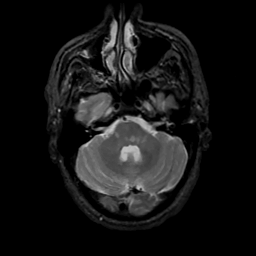

MR Study #13, May 19, 1991 -- Slice #12